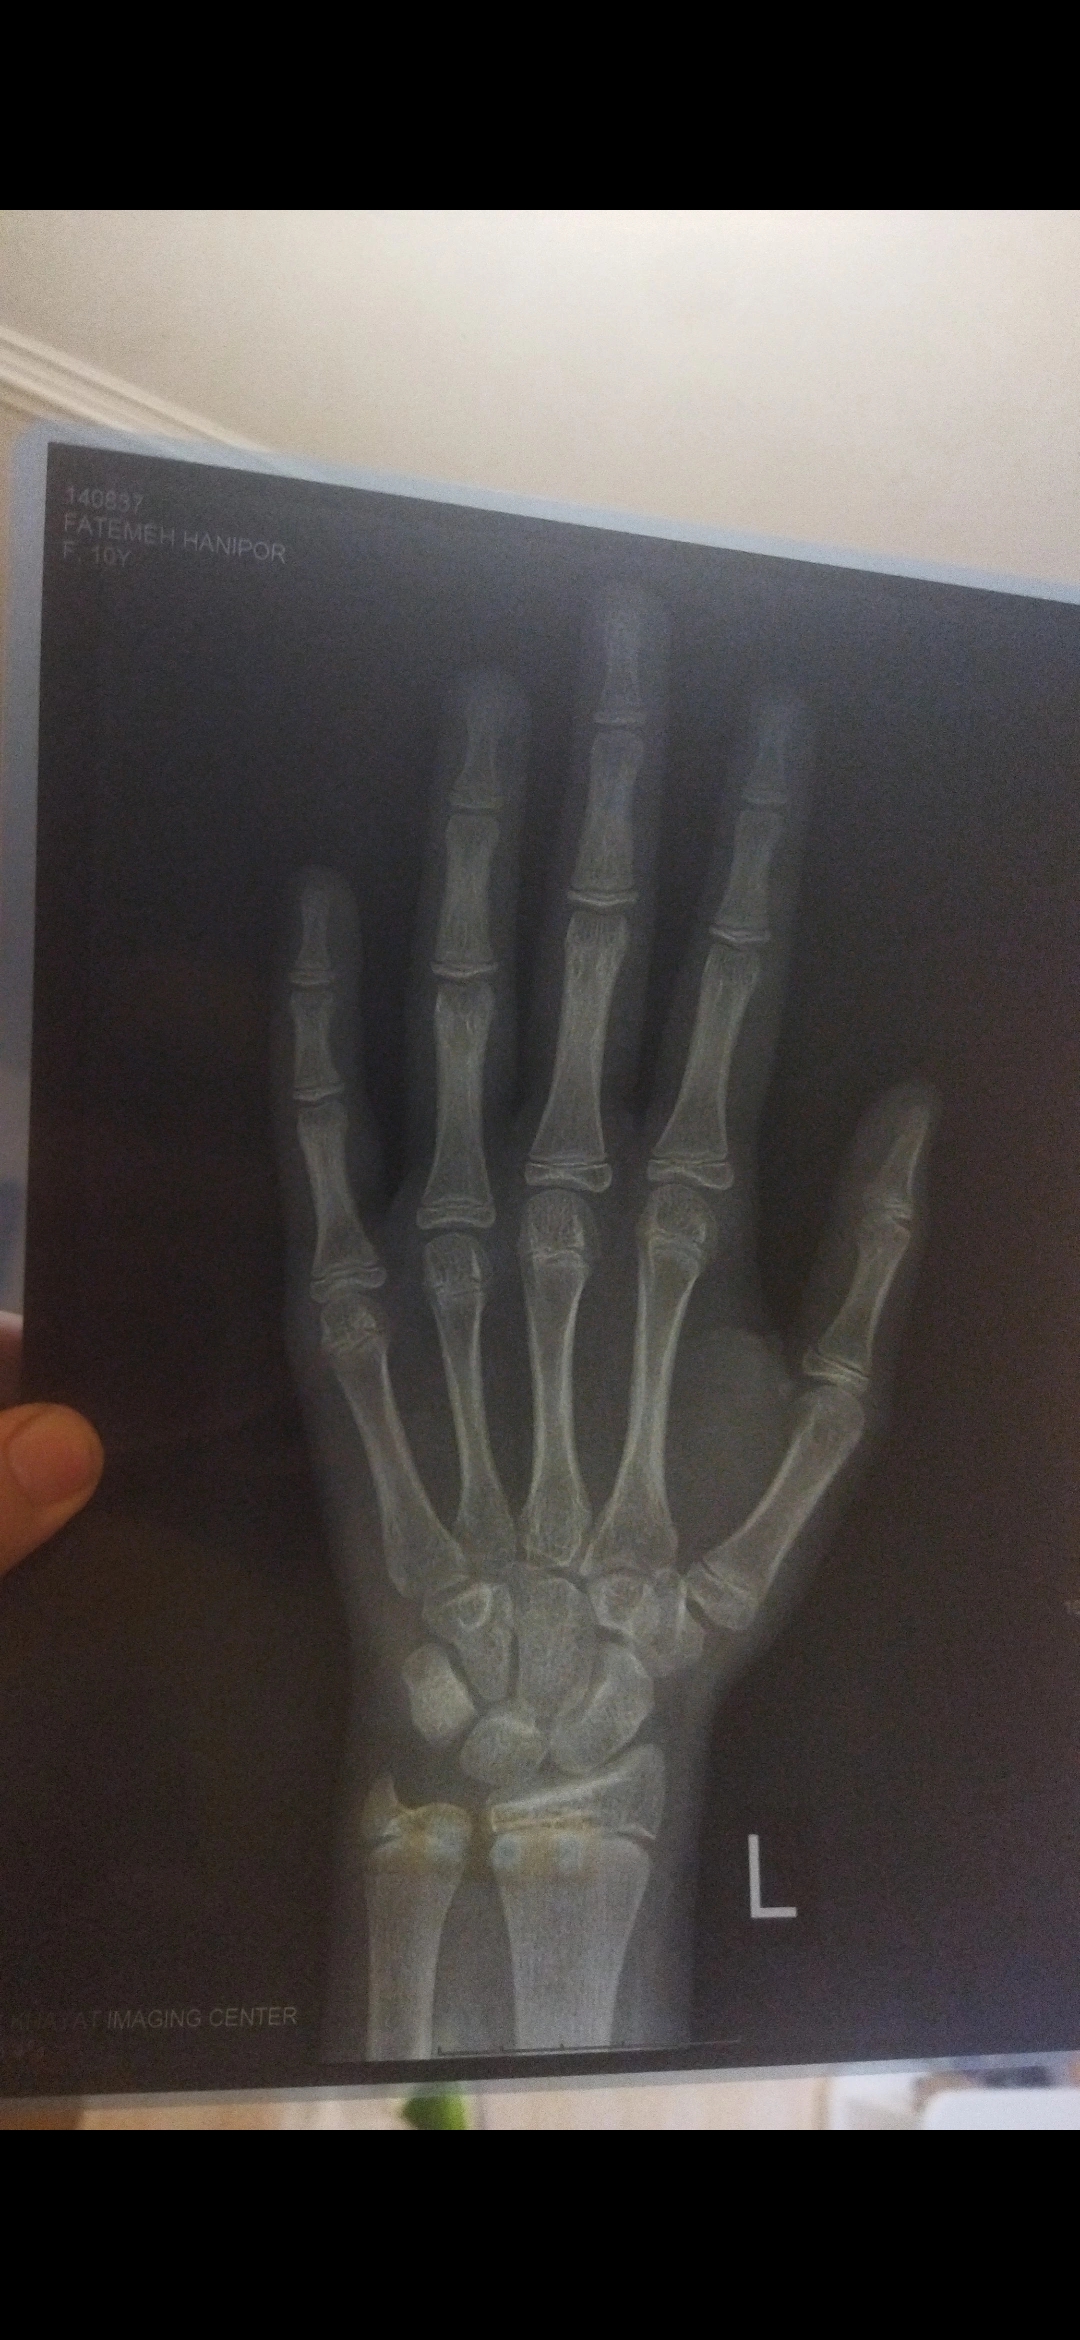

سلام مامان مهرعکس مچ دست دخترمه دوماهه پریودشده متولدبرج 1سال 94بردم دکترفقط مکمل وکلیسم دادقدش 154وزنشم 46کیلودکترش بهم گفت تا160میرسه قدش ولی اگه بخوام یماه دیگه میتونه براش امپول رشدبزنه نظرت چیه طبق عکسش جای رشدداره یانه

به نظرم سن استخوتنیش ۱۱.۵ تا ۱۲ سال حدودا

جای رشد که بله خیلی زیاد داره هنوز سنی نداره. حتما بالا ۱۶۲ میشه